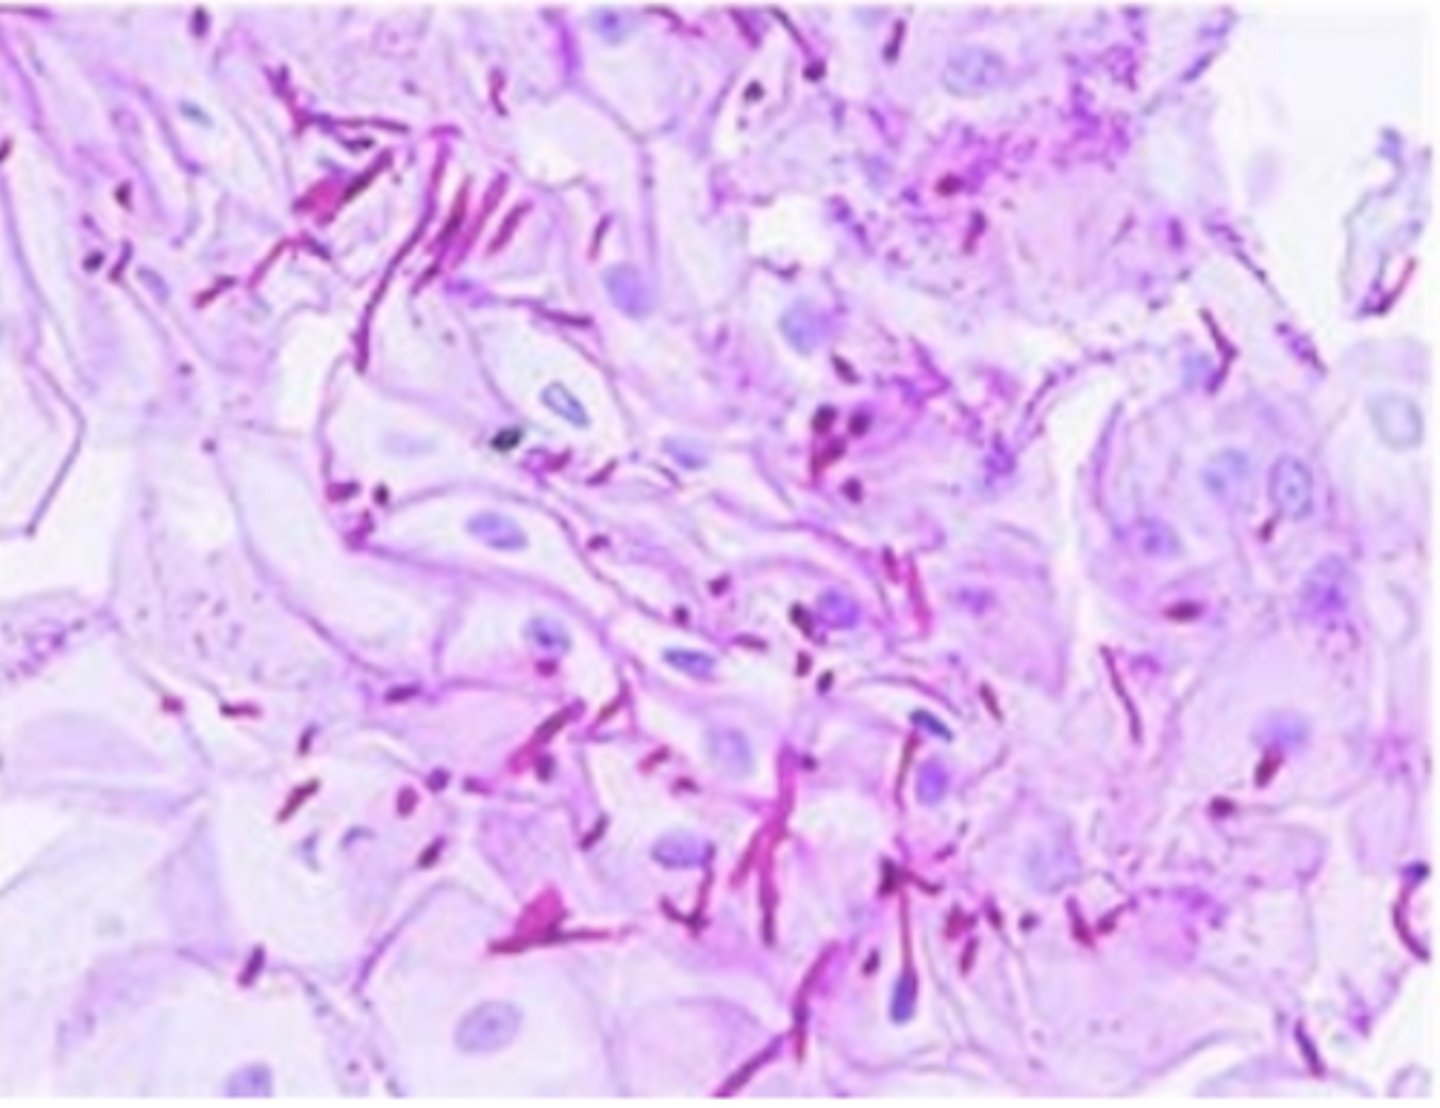

Periodic Acid Schiff (PAS)

Stains carbohydrates pink/red

<p>Stains carbohydrates pink/red</p>